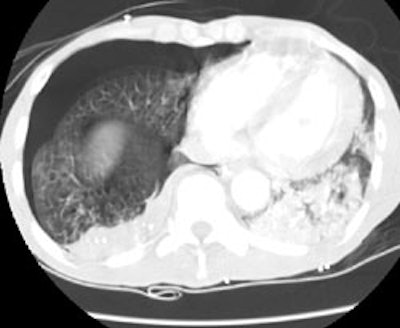

CT PE exam: Alternative diagnosis

The CT PE exam shown below demonstrates bilateral air space disease and a right pneumothorax that was not evident on the patients CXR (Click CXR to enlarge). The CT-PE exam can suggest an alternative diagnosis to explain the patients symptoms in 10-50% of cases.